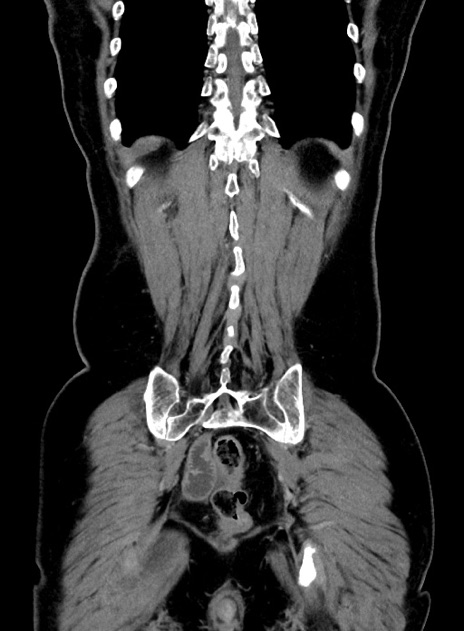

症例9(冠状断像)

【症例】 60歳代女性

【主訴】むかつき、みぞおちの痛み

【現病歴】3日前よりむかつきがあり、食事がとれない。

【既往歴】糖尿病

【身体所見】発熱なし、心窩部圧痛軽度あるも、腹膜刺激症状なし。

【データ】WBC 7400、CRP 1.92